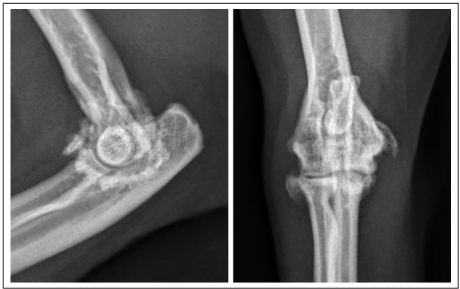

- 결과 2: 영상 진단의 유용성 방사선 검사만으로는 질병의 전체적인 상태를 파악하기 어려웠습니다. CT 촬영을 진행한 10개의 팔꿈치 중 7개에서 방사선으로는 확인되지 않았던 추가적인 문제, 특히 **관절 내 유리체(mineralized bodies)**가 5개의 팔꿈치에서 발견되었습니다. 또한, 방사선 소견이 경미했던 4개의 팔꿈치에 대해 초음파 검사를 시행한 결과, 힘줄 주변의 미세한 염증과 초기 단계의 광물 침착을 발견할 수 있어 조기 진단에 대한 초음파의 가능성을 확인했습니다.